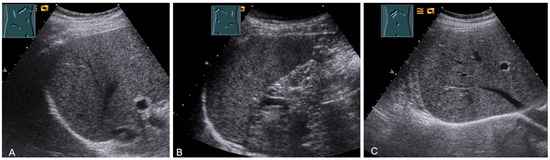

For sonographic evaluation of the diaphragm, the patient should be in the supine position with the head angled at 30°, as this position reduces examiner variability, increases reproducibility, and enhances excursion [52,53]. The supine position increases any paradoxical movement and at the same time limits any compensatory active expiration through the anterior abdominal wall that may mask paralysis [52]. From lateral intercostal approaches, the right diaphragm should be examined through the liver window and the left diaphragm through the spleen window (Figure 29) [53]. Limitations of left diaphragm visualization due to the small acoustic window can be reduced by adopting a more coronal view, parallel to the ribs. Pathologic conditions such as splenomegaly or hepatomegaly with a large left lobe facilitate the evaluation of the left diaphragm [52]. In addition, the right-sided diaphragm can be visualized in the subcostal transhepatic section with cranial tilt of the transducer (Figure 29).

Figure 29.

Visualization of the right-sided (A) and left-sided diaphragm (B) with the lateral intercostal view and of the right-sided diaphragm with the subcostal view (C).

Border shadow artifacts may indicate an apparent diaphragmatic gap, which disappears when the transducer position is changed (Figure 30).